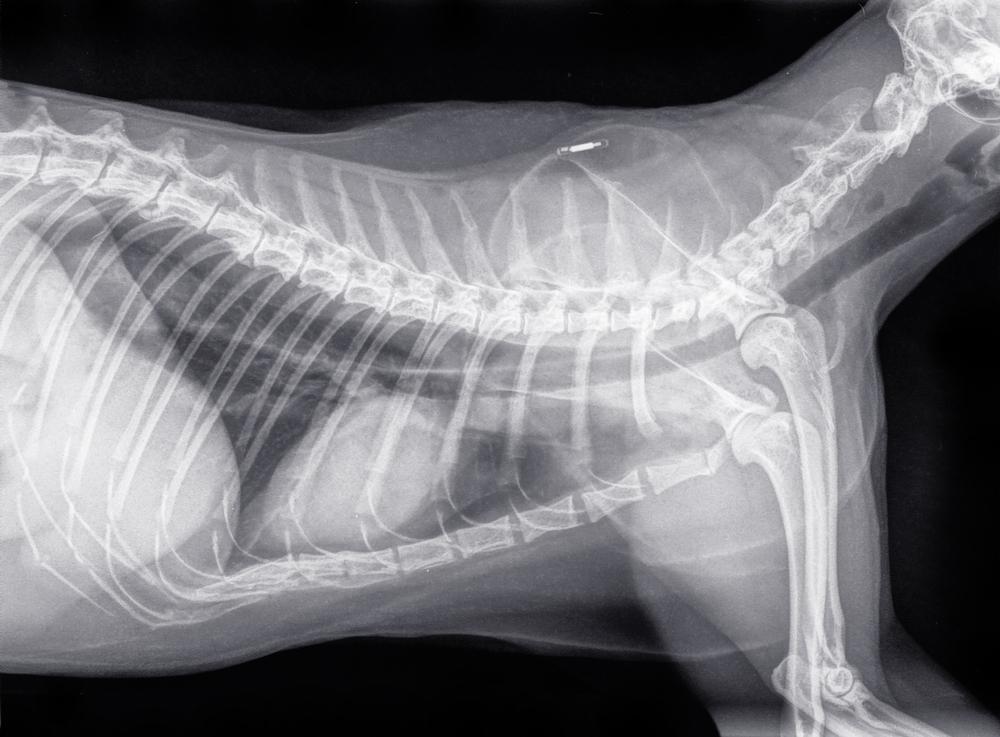

УЗИ, показывающее изменение в очертаниях и размерах, а также наличие кист и других образований;

рентген, фиксирующий место развития и форму течения нарушения.